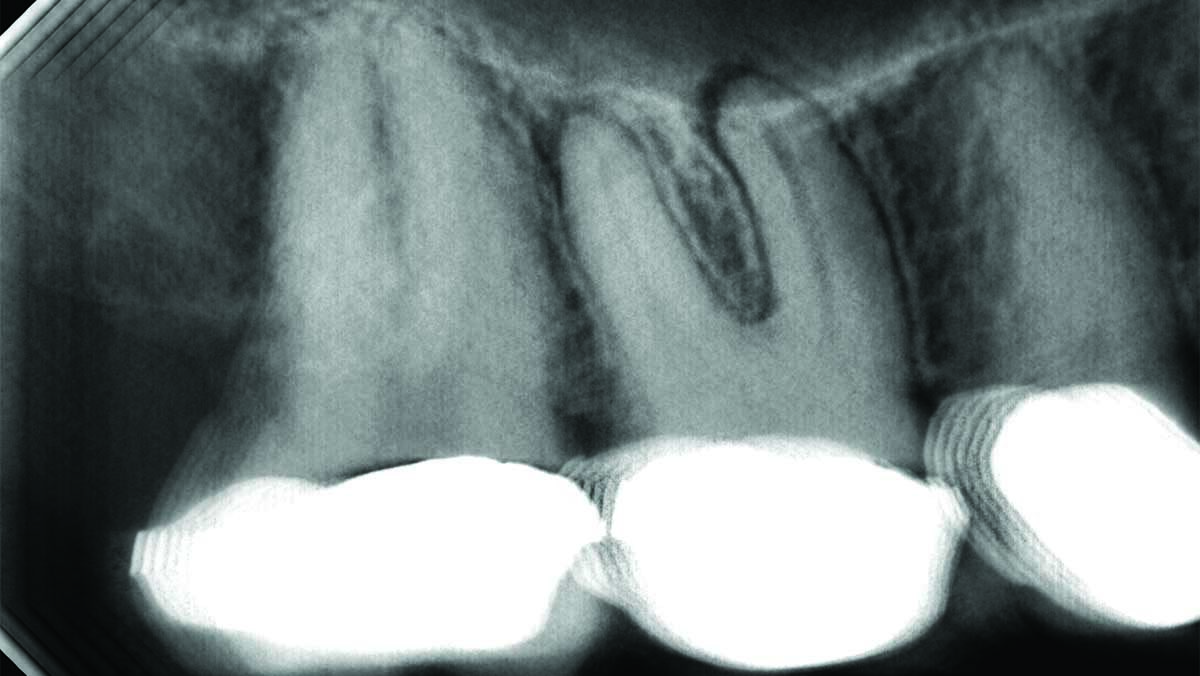

A Paradigm Shift in Dental Imaging: Stationary Intraoral Tomosynthesis

Landwehr-fig_3B alternate text for this image

An accurate endodontic diagnosis is based on a variety of clinical tests, including thermal and electric pulp testing, percussion, bite stick, periodontal probing, and palpation. However, each of these subjective tests is prone to both false positive and false negative responses that could result in the inability to get an accurate diagnosis or the treatment … Read more